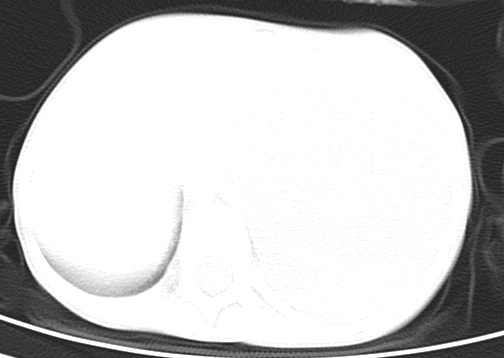

患儿 女 4岁,发热 咳嗽 胸透 考虑:左侧脓胸

不排除---肠源性囊肿或淋巴瘤

左侧胸廓内见大量密实阴影,肺尖部尚有少量肺组织影,纵膈明显受压移位,肋骨未见明显受侵征象,虽然病人年龄较小,但如此大量的“积液”,还是要警惕,不同意一般感染,可结合穿刺脱落细胞学检查。

左侧张力性大量胸腔积液压迫性肺不张、感染;建议治疗后复查。

左侧大量胸腔积液,原因待查。